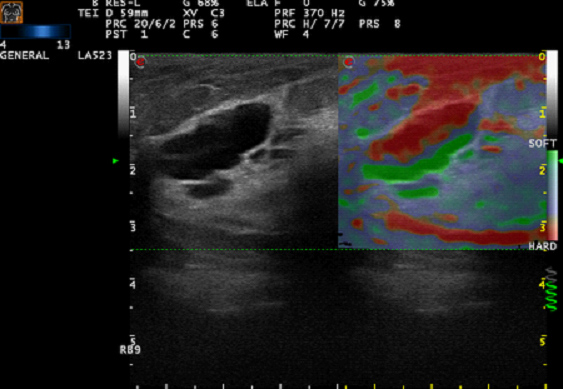

在超声检查时,利用外加在探头上的压力变动、利用脉冲声压对组织的压力变化,利用心搏或呼吸活动对邻近组织传导的压力或者导管式超声探头在心腔或血管腔内所受到变化的血压,均可使合适的脏器或病灶发生弹性形变,或称应变。利用应变量大小经彩色(或灰阶)调制成像,并与常规的声像作比较的方法,称超声弹性成像。

组织弹性成像可有效鉴别实质性肿瘤的良恶性,对于恶性病变诊断具有较高的特异性和敏感性。目前其主要应用于乳腺、前列腺、甲状腺等小器官,尤其在乳腺疾病方面研究更为深入,技术更加成熟。此外,组织弹性成像还可应用于肝纤维化的诊断、局部心肌功能评价以及高强度聚焦超声(HIFU)与射频消融(RFA)引起的损害的检测与评估。心肌弹性成像能够准确客观地对局部心肌功能进行定量评价,具有高精度、高分辨率(时间、空间)、角度无关性以及很好的重复性等优点,可应用于心肌梗死和心肌缺血的定位。